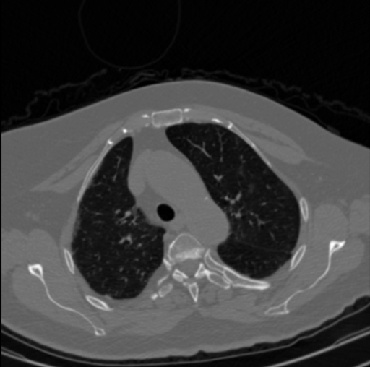

Early and reliable COVID-19 diagnosis based on chest 3-D CT scans can assist medical specialists in vital circumstances. Deep learning methodologies constitute a main approach for chest CT scan analysis and disease prediction. However, large annotated databases are necessary for developing deep learning models that are able to provide COVID-19 diagnosis across various medical environments in different countries. Due to privacy issues, publicly available COVID-19 CT datasets are highly difficult to obtain, which hinders the research and development of AI-enabled diagnosis methods of COVID-19 based on CT scans. In this paper we present the COV19-CT-DB database which is annotated for COVID-19, consisting of about 5,000 3-D CT scans, We have split the database in training, validation and test datasets. The former two datasets can be used for training and validation of machine learning models, while the latter will be used for evaluation of the developed models. We also present a deep learning approach, based on a CNN-RNN network and report its performance on the COVID19-CT-DB database.